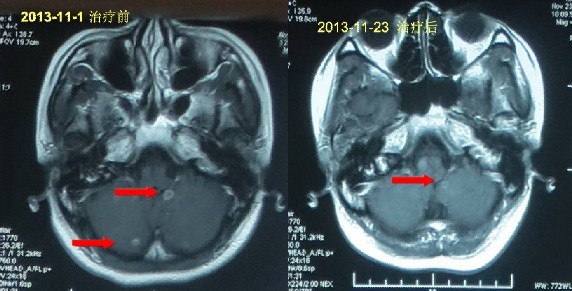

患者姓名:马小姐,33岁,确诊为肺癌

简要病史:经过朋友推荐来到广州中医药大学金沙洲医院医院进行检查,检查后诊断右肺上叶肺癌,纵膈淋巴结转移,腰椎转移,心包积液,多发骨转移,多发脑转移,手术风险很大,朋友、家人都着急了,患者自己也慌了,听从专家的安排,进行多学科综合治疗治疗:WB-1无创全身热疗系统+P53基因治疗,两个疗程之后,患者健康恢复显著,半个月患者出院。